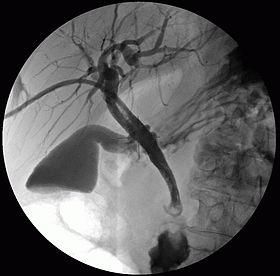

Percutaneous transhepatic cholangiography (PTHC or PTC), percutaneous hepatic cholangiogram, or percutaneous transhepatic cholangiography and drainage (PTCD) is a radiological technique used to visualize the anatomy of the biliary tract. A contrast medium is injected into a bile duct in the liver, after which X-rays are taken. It allows access to the biliary tree in cases where endoscopic retrograde cholangiopancreatography (ERCP) has been unsuccessful. Initially reported in 1937, the procedure became popular in 1952.[1][2]